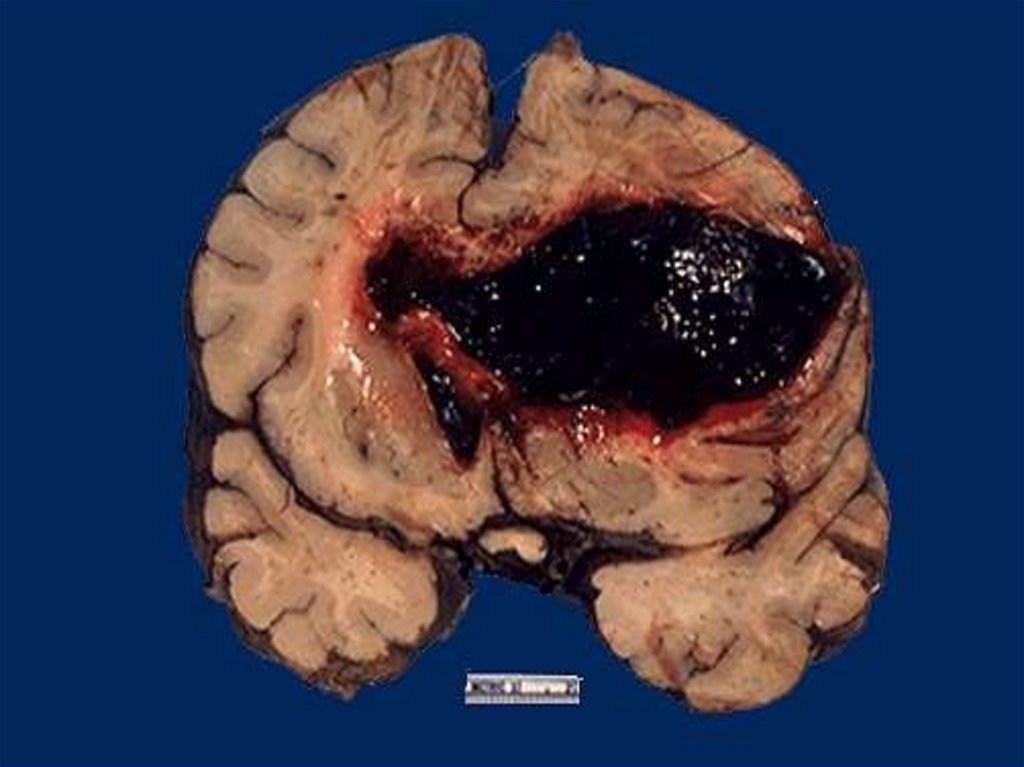

43. Кровоизлияние в головной мозг

7. Эмболия инородными телами

Кровоизлияние – при

кровотечении

кровь

накапливается

в

тканях.